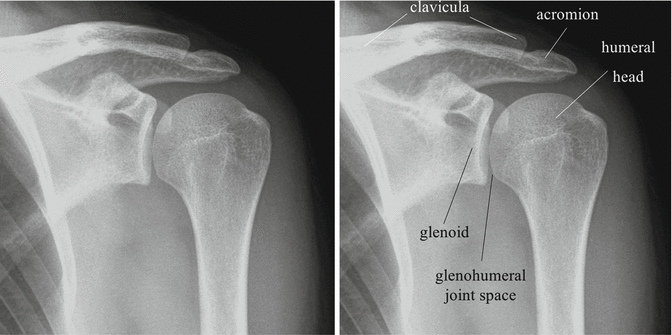

The shoulder series is fundamentally composed of two orthogonal views of the glenohumeral joint including the entire scapula. This effusion suggests intra articular fracture.

Shoulder dislocation is a term often used loosely to indicate dislocation of the head of the humerus from the glenoid of the scapula. The extension of the shoulder series depends on the radiography department protocols and the clinical indications for imaging. The tendon of the subscapularis muscle attaches both to the lesser tubercle aswell as to the greater tubercle giving support to the long head of the biceps in the bicipital groove.

Do not confuse with dislocation. X ray films cannot diagnose muscle or tendon injuries. An effusion or haemorrhage into the joint displaces the humeral head inferiorly.